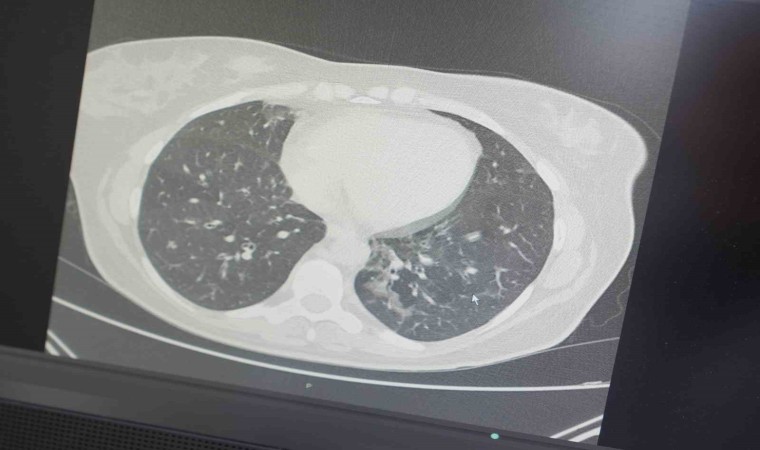

İnsanların Covid-19 öncesi yaptığı ağır sporları, artık kovid-19 virüsü aldıktan sonraki hayatında yapamadığını belirten Profesör Özkaya, "Spor yapmaya çalışanlar ise ciddi akciğer ve kalp sorunu yaşayabiliyorlar. Covid-19 sonrası başta akciğer ve kalp kılcal damarlardaki kalıcı hasar, ağır egzersiz sonrası kanın yeterli oksijen sunumunu sağlanamaması sonucu ani ölümle kadar gidebilen ciddi şikayetlere neden oluyor. Özellikle profesyonel sporculardan ve halı sahalarda amatör sporcularda ani ölümlerin arttığını görüyoruz. Bu ağır spor ve egzersiz, birde mevcut kış mevsiminin getirdiği soğuk hava ile birleşince özellikle Covid-19 salgını sonrası ani ölümlere neden olduğunu öngörebiliyoruz. Kapalı ve havalandırması yetersiz spor salonlarından çok sayıda zatürre geliştiğini de görüyoruz. Özellikle zatürre genç hastalarda ciddi sayıda artışlar var. Kapalı, havalandırması bozuk, kalabalık spor salonları ve toplu seyahatlerden sonra gençler kolayca zatürre oluyorlar. Özellikle Covid-19 pandemisinden etkilenen vatandaşlarımızın, kış mevsiminde ağır egzersiz, soğuk hava ve halen aramızda olan başta virüs olmak üzere diğer solunum yolları patojenlerine dikkat etmeleri gerekiyor" şeklinde konuştu.